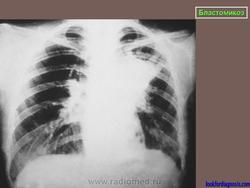

Рентгенологически отмечаются выраженные изменения лимфатических узлов средостения, очаговые инфильтраты, в некоторых из них развиваются каверны с неправильными контурами. При диссеминации процесс захватывает многие органы, эти формы часто заканчиваются гибелью больного.